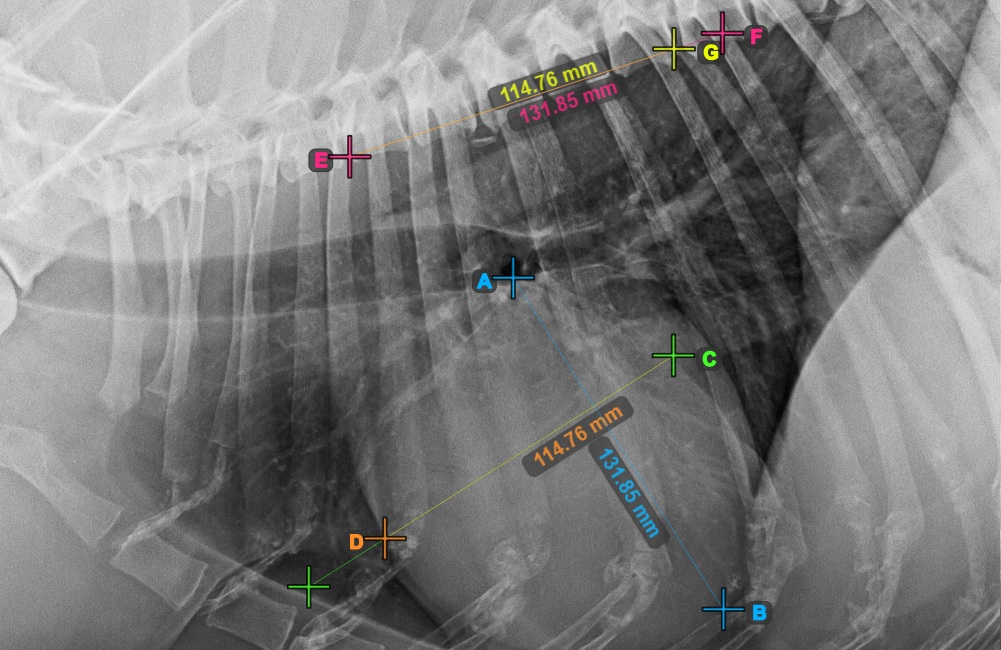

Identify the beginning of the T4 vertebra (the fourth vertebral body of the spine), counting from the initial point of the spine. Mark the beginning of the T4 vertebrae to continue the measurement. The software will draw lines from the marked point along the spine. The length of the lines depends on the measured long and short axes of the heart.

The image below represents the typical placement of the point at the beginning of the fourth vertebral body of the spine.

Before proceeding with the required VHS calculations, make sure that the lines are placed precisely along the vertebrae.

Count the number of vertebrae along the line representing the short axis on the spine. Specify the required vertebrae count in the Vertebrae Count input field in the advanced measurement mode toolbar.

Press Calculate VHS Score to perform the required calculations for the VHS measurement. The VHS score will be shown in the advanced measurement mode toolbar. Additionally, the VHS score will be labeled on the image, as part of the measurement.